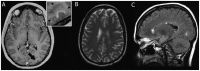

Purpose of review: This article summarizes the pathologic features of multiple sclerosis (MS) and other inflammatory demyelinating diseases and discusses neuropathologic studies that have yielded novel insights into potential mechanisms of demyelination.

Recent findings: The pathologic hallmark of MS consists of focal demyelinated plaques within the CNS, with variable degrees of inflammation, gliosis, and neurodegeneration. Active MS lesions show a profound pathologic heterogeneity with four major patterns of immunopathology, suggesting that the targets of injury and mechanisms of demyelination in MS may be different in different disease subgroups. Recent pathologic studies have suggested that the subarachnoid space and cortex may be initial sites and targets of the MS disease process, that inflammatory cortical demyelination is present early in MS, and that meningeal inflammation may drive cortical and white matter injury in some MS patients.

Summary: MS is heterogeneous with respect to clinical, genetic, radiographic, and pathologic features; surrogate MRI, clinical, genetic, serologic, and/or CSF markers for each of the four immunopatterns need to be developed in order to recognize them in the general nonbiopsied MS population. Inflammatory cortical demyelination is an important early event in the pathogenesis of MS and may be driven by meningeal inflammation. These observations stress the importance of developing imaging techniques able to capture early inflammatory cortical demyelination in order to better understand the disease pathogenesis and to determine the impact of potential disease-modifying therapies on the cortex.